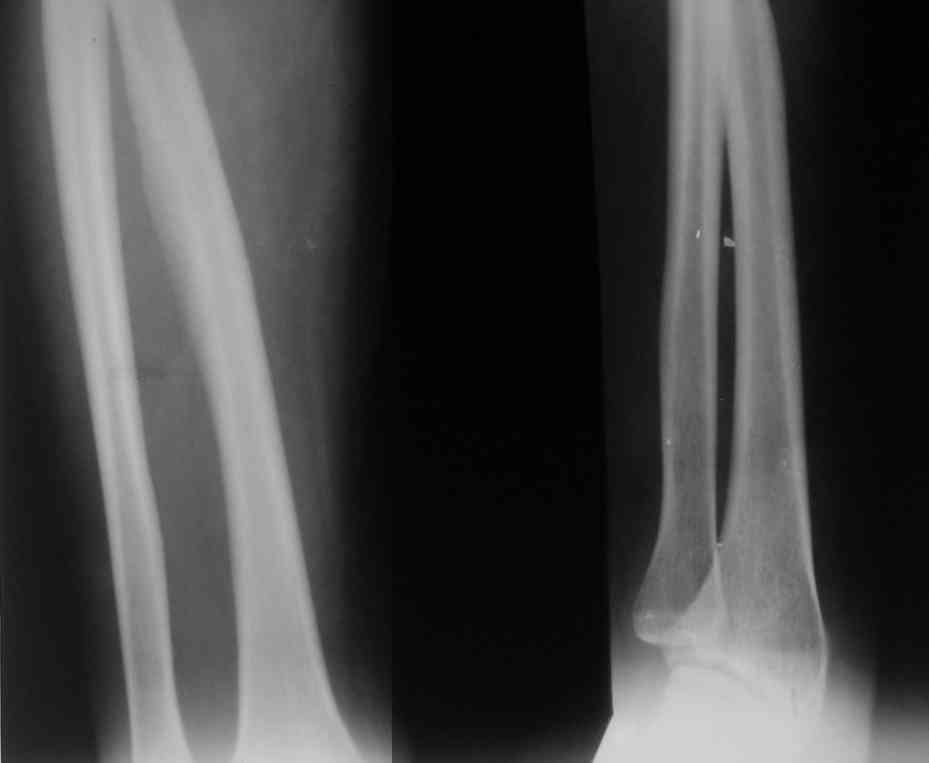

Уважаемые коллеги,помогите определиться с диагнозом и лечением.Ко мне обратилась знакомая 52 лет,с жалобами на интенсивные боли в левом предплечье.Больна около 5-6 лет.

За последний год боли стали более интенсивными,вынуждена носить руку на косынке, иногда не может уснуть из-за болей,практически не может работать. Боли ноюшие, изматывающие, продолжающиеся 5-8 дней, затем, после покоя, применения анальгетиков - стихают. Боль четко локализуется в проекции лучевой кости. Отека, признаков воспаления нет.

Пальпация безболезненная,пальпируется над лучевой костью еле заметная "впадина". В анамнезе - в детстве стояла на учете и лечилась у фтизиатора, с учета снята более 20 лет назад. В настоящее время осмотрена фтизиатром. Туберкулез исключается, Манту 13 мм. Анализы крови, мочи-без патологии. На рентгенограммах веретенообразное утолщение лучевой кости и истончение коркового слоя. Я склоняюсь к диагнозу склерозирующего остеомиелита Гарре. Склерозирующий остеомиелит ли это? Нужна ли биопсия? Какие есть современные схемы лечения? Заранее благодарен.

Уважаемый коллега! Во-первых, рентгенограммы выполнены не стандартно. Необходимо сделать рентгенограммы предплечья в прямой и боковой проекции с захватом одного из прилежащих суставов, это общее правило. Во-вторых, по представленным рентгенограммам патологических костных изменений, в т.ч. склезирозирующего остеомиэлита не определяется. Утолщение в с\3 диафиза - физиологическая норма (место прикрепления межкостной мембраны). С уваж. Е.М.

Коллега, если тут не скрыта какая-то неврология-корешковая симптоматика? Сделайте несколько косых снимков, не исключена остеоидная остеома. При подозрении на конкретный участок пошли больного на КТ.